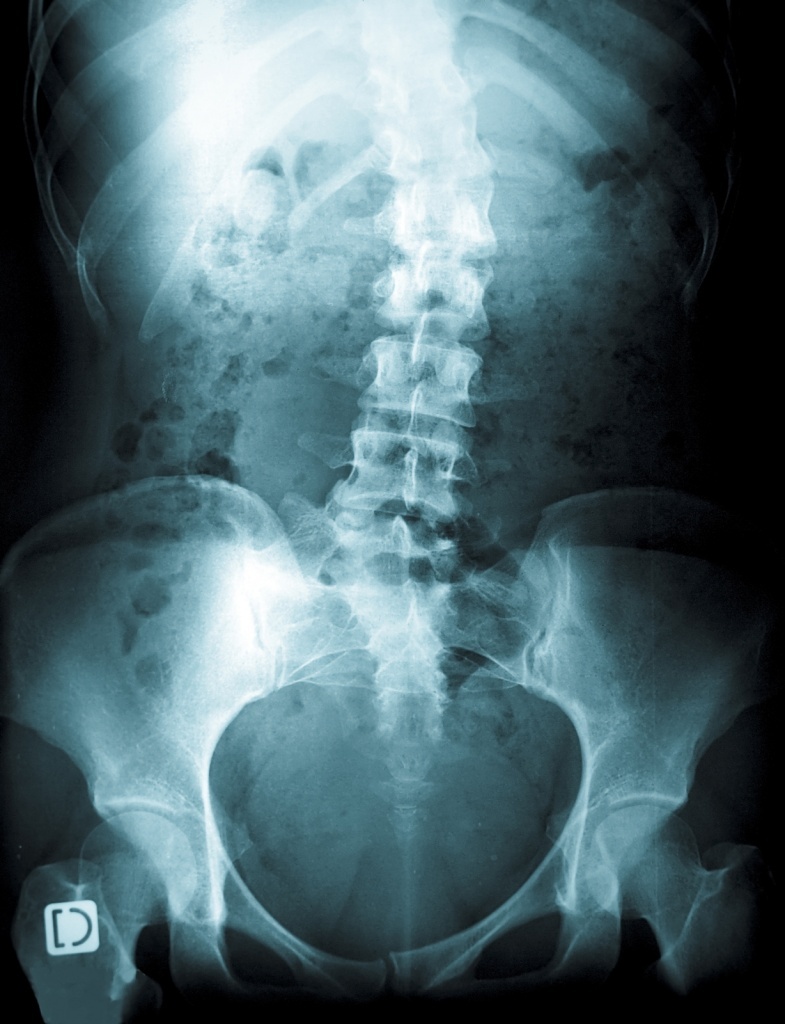

Рентгенограмма позвоночника при сколиозе

Костные деформации при сколиозе